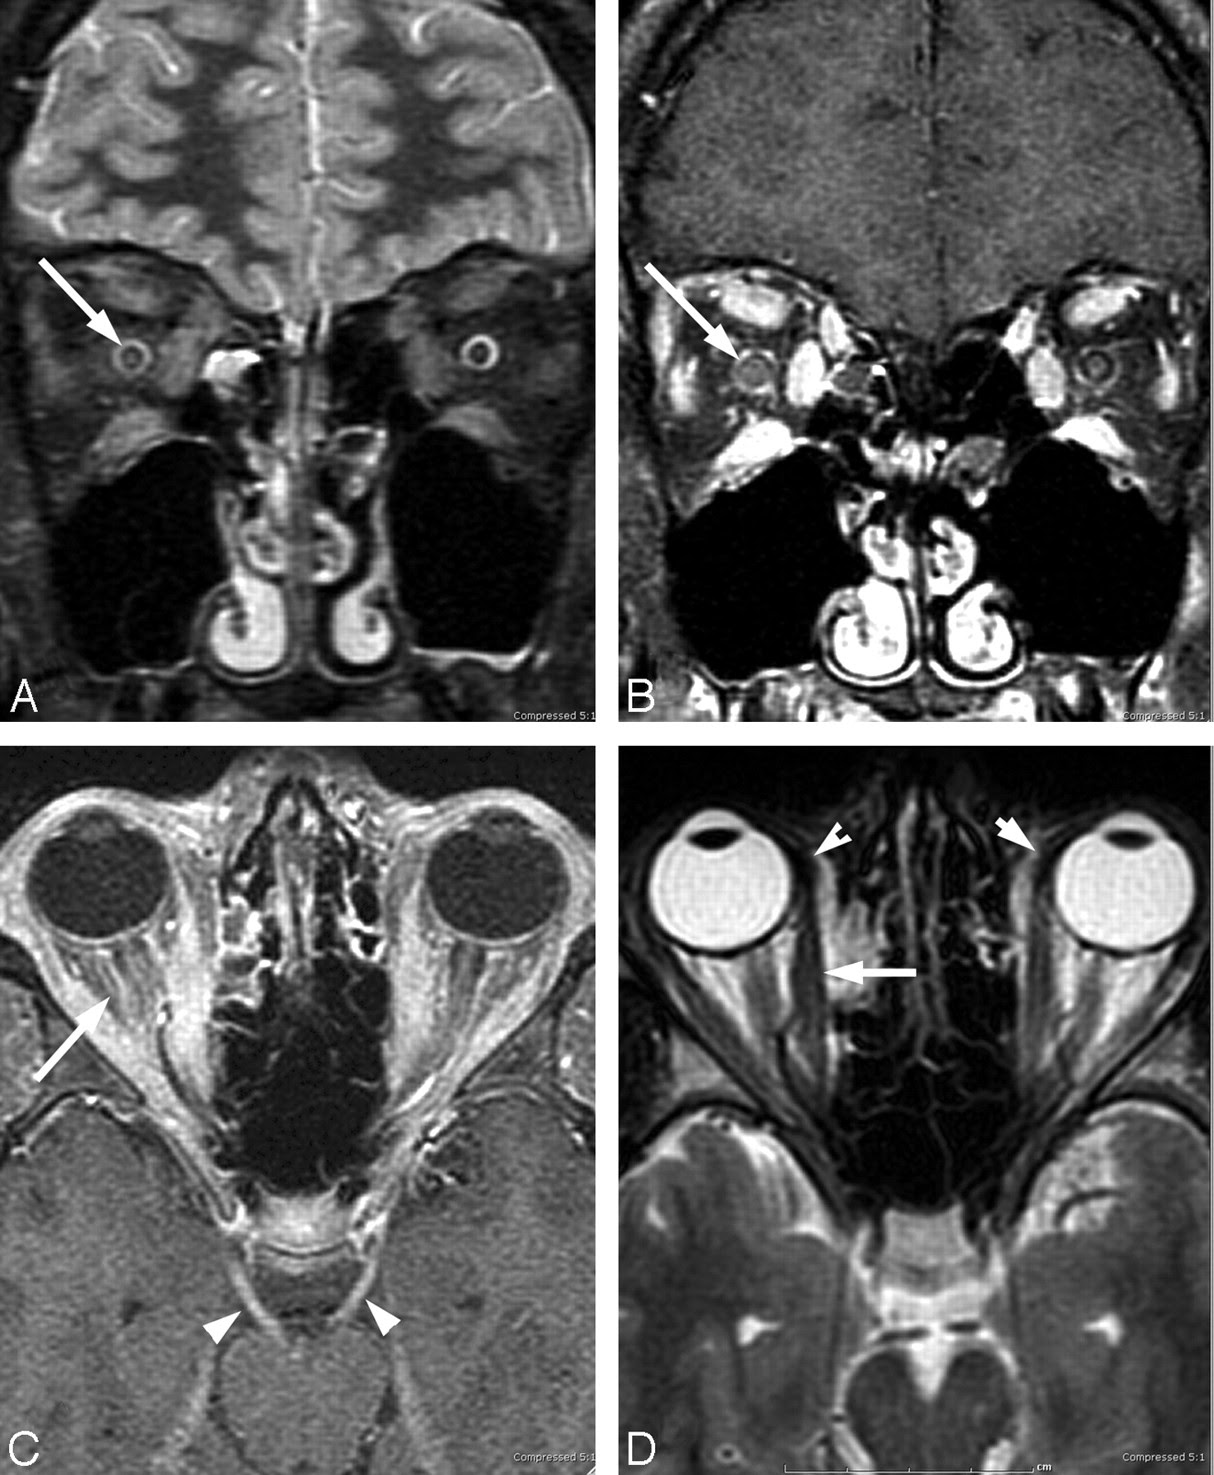

In a person with MS the lesions are usually very specific and localized in certain areas of the brain but in Lyme Disease they can be all over and very non-specific. Lyme disease brain MRI scans may also show brain involvement Interestingly Lyme disease brain lesions sometimes show up on brain scans and look similar to multiple sclerosis lesions. Brain aneurysm a bulge in an artery in your brain Brain AVM arteriovenous malformation arteriovenous malformation an abnormal formation of brain blood vessels.

Additionally MS and Lyme Disease can both be relapsing diseases. According to some sources this percentage may even be higher since thousands of cases are likely to remain undiagnosed every year. Lyme neuroborreliosis is one of the chronic manifestations of Lyme disease and is caused by the neurotropic spirochete Borrelia burgdorferi.